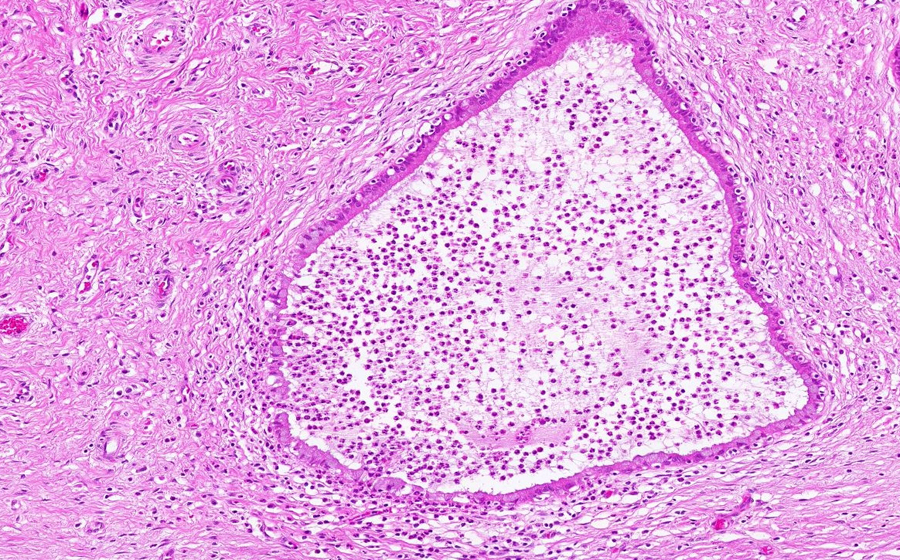

Image 2 - 50X

Slide 3 - Image 2